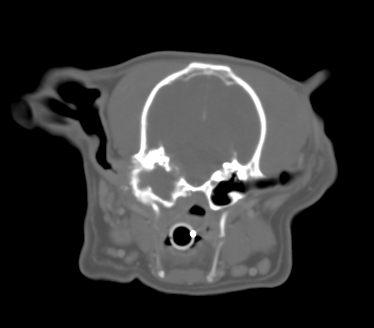

“Fencer” is a 9 year old Male (neutered) WHWT with a 12 month history of intermittent bilateral otitis externa. Fencer has had a left sided head tilt and also yelps with pain when yawning and refuses to eat his biscuits. Initial investigations are unrewarding with little response to NSAID therapy and topical ear medication based on culture/sensitivity. Fencer is anaesthetised and a CT examination performed (see below)

CT image

The left tympanic bulla is distorted and irregularly enlarged with areas of irregular bony proliferation and also osteolysis including erosion of the medial bulla wall towards the cranial vault. Some localised meningeal enhancement is visible suggestive of a meningitis. >>back to quiz

The most likely diagnosis is Cholesteatoma which is becoming increasingly frequently diagnosed. Other ddx would include a slowly growing primary middle ear neoplasm or otitis media (less likely).